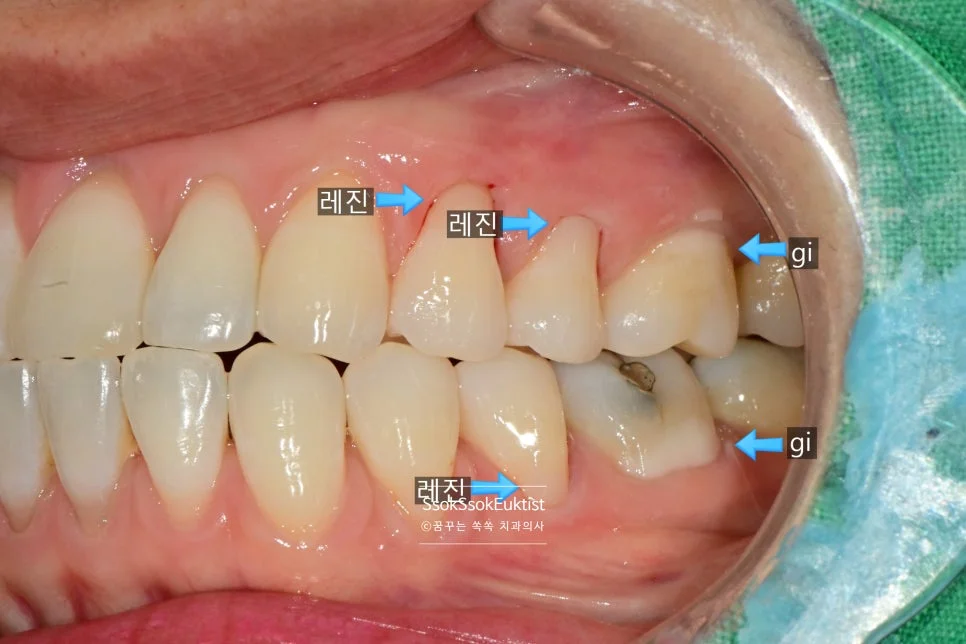

GI(글라스아이오노머)를 이용한 치경부 마모증 치료

GI 치료 전 — 대부분 V자, 일부 U자 형태

형태를 보면 대부분 V자인데 하나 정도만 U자 형태를 보이고 있습니다. 이런 경우 강한 칫솔질이 치경부 마모증을 악화시켰다고 볼 수 있습니다!

이 사례에서는 GI(Glass Ionomer, 글라스 아이오노머)로 충전을 시행하였는데요.

GI를 이용한 치경부 마모증 충전 중

그러고는 GI를 이용해 치경부 마모증을 충전해 주는데요.

어떤가요? GI를 이용한 충전도 꾀나 괜찮나요?

우리 치과에서는 가장 비싸고 심미적인 GI를 사용하고 있습니다^^

한편 그런데 말입니다… 사실 GI의 경우 색상이 거진 정해져 있어 치아가 GI의 색과 유사한 색이면 이렇게 예쁘게 치료가 가능하고, 치아가 보다 밝거나 어두우면 색상이 좀 안 맞아질 수 있습니다^^